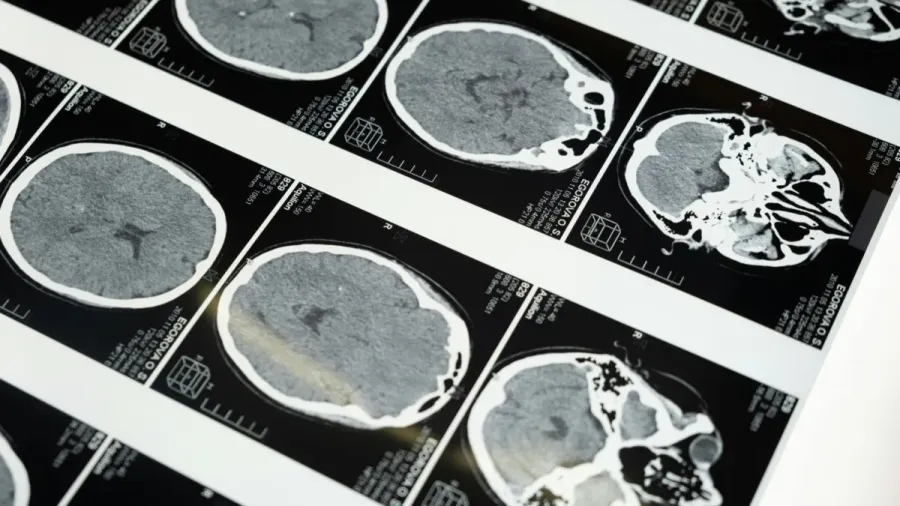

The 1.5T magnetic resonance imaging (MRI) systems market in India is growing rapidly as hospitals and diagnostic centres seek more accurate and efficient imaging solutions.

“The expanding adoption of 1.5T MRI systems in India is driven by the need for reliable, cost-effective diagnostic imaging solutions that support clinicians in managing neurological, musculoskeletal, and oncological conditions,” said Sarvesh Kumar, medical devices analyst at GlobalData.